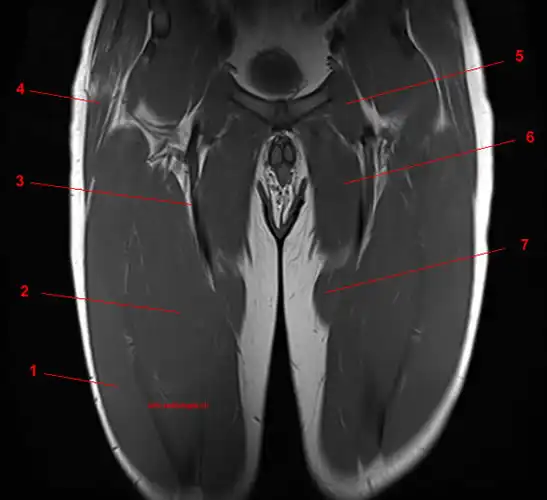

MRI Screening Of Thigh

What is MRI Screening of Thigh?

An MRI of the thigh shows the bone and surrounding cartilage, tendons, ligaments, muscles, and blood vessels. An MRI thigh scan diagnoses leg discomfort and a thigh fracture. This test detects abnormal thigh muscle or soft-tissue growth.